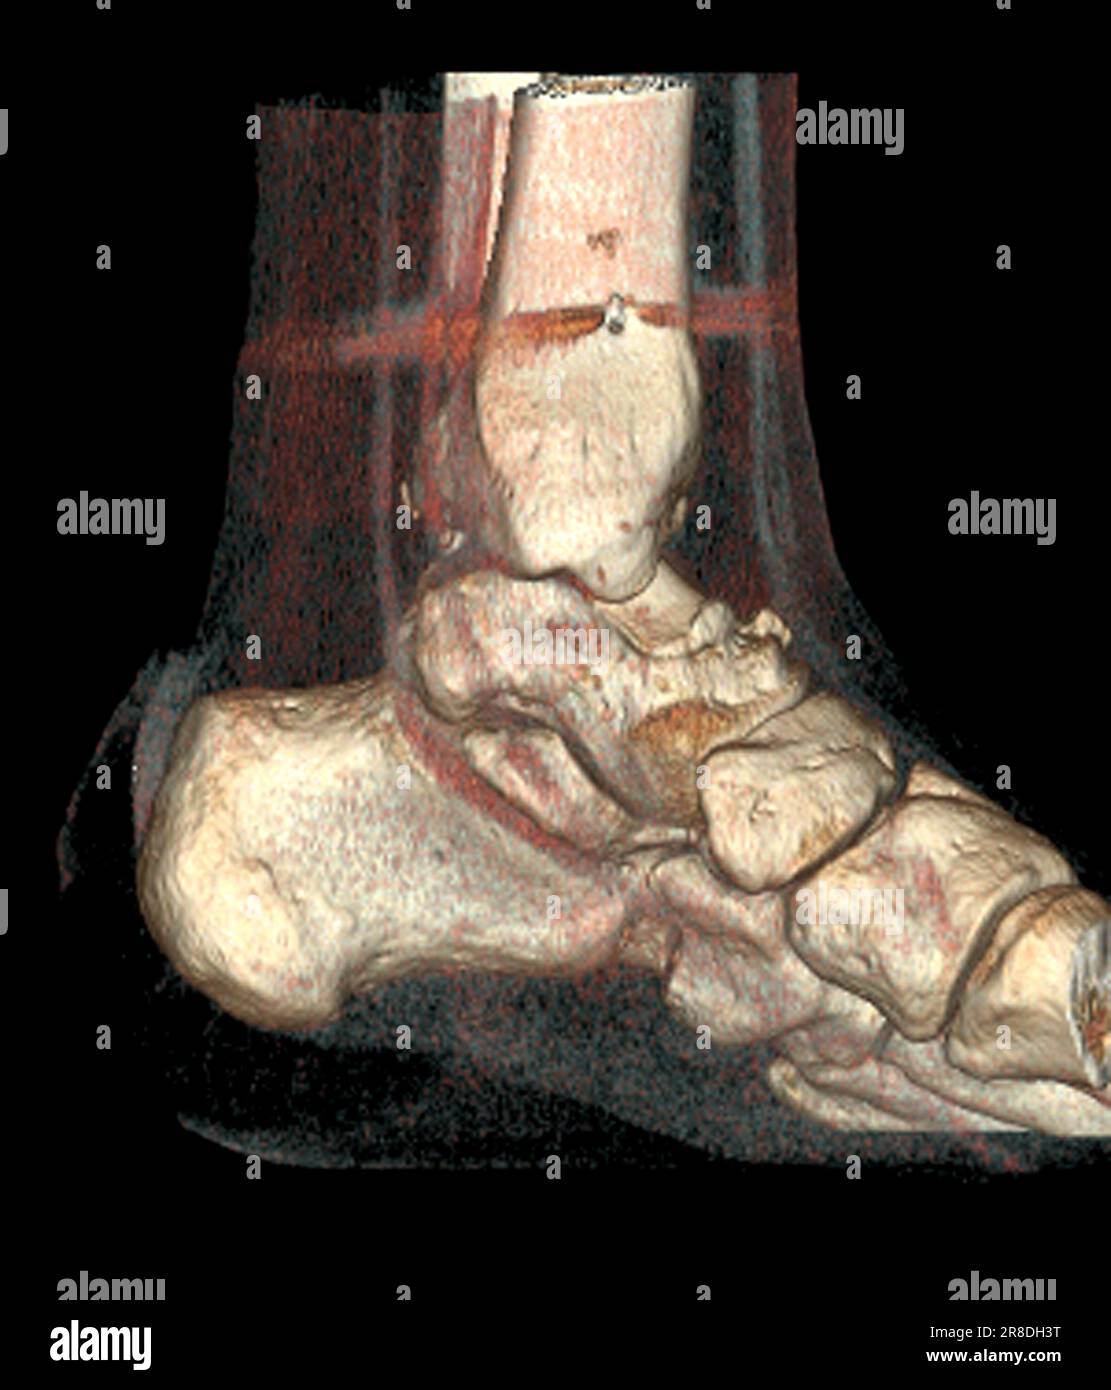

From www.alamy.com

Coloured 3D computed tomography (CT) scan of the pinned ankle of a 32 Calf In Bone Fracture The proximal tibia is the upper portion of the bone where it widens to help form the knee. Fibula fractures occur around the ankle, knee, and middle of the leg. A broken leg (leg fracture) is a break or crack in one of the bones in your leg. Here, health care providers typically evaluate the injury and immobilize the leg. Calf In Bone Fracture.

Coloured 3D computed tomography (CT) scan of the pinned ankle of a 32 Calf In Bone Fracture The fibula, or calf bone, is a small bone located on the outside of the leg. Here, health care providers typically evaluate the injury and immobilize the leg with a splint. Healthcare providers also call broken legs fractured legs. There are three bones in your leg, including. A fibula fracture describes a break in this bone. Treatment can vary, but. Calf In Bone Fracture.